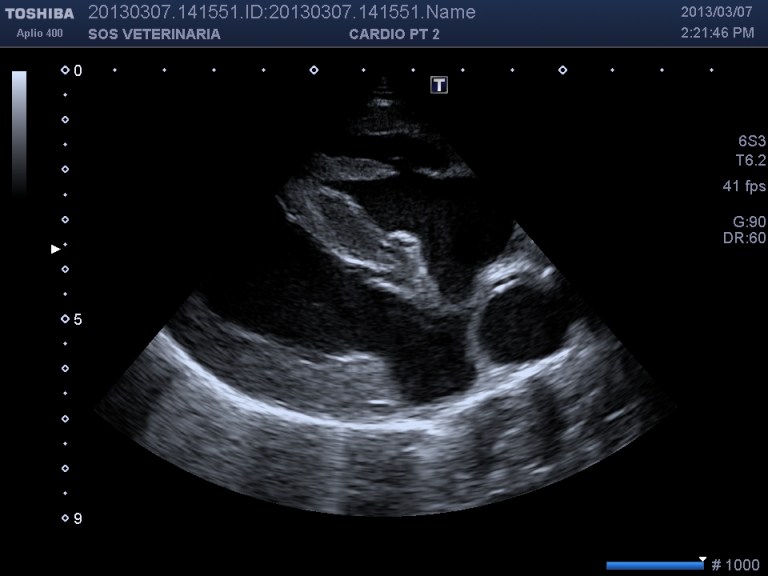

Ecco i filmati piu’ significativi osservare il flusso laminare che scorre parallelo alla parete laterale dell’arteria polmonare non piu’ continuo ma annullato in sistole dalla gittata in polmonare ,nel terzo filmato si vede l’ampolla del dotto